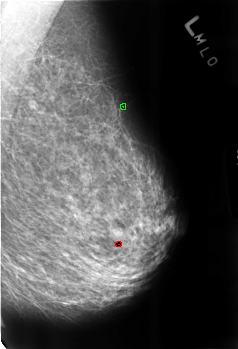

B_3225_1.LEFT_MLO

LEFT_MLO LINES 4536 PIXELS_PER_LINE 3088 BITS_PER_PIXEL 12 RESOLUTION 50 OVERLAY

FILE: B_3225_1.LEFT_MLO.OVERLAY

TOTAL_ABNORMALITIES 2

ABNORMALITY 1

LESION_TYPE CALCIFICATION TYPE COARSE-ROUND_AND_REGULAR-LUCENT_CENTER DISTRIBUTION N/A

ASSESSMENT 2

SUBTLETY 4

PATHOLOGY BENIGN_WITHOUT_CALLBACK

ABNORMALITY 2